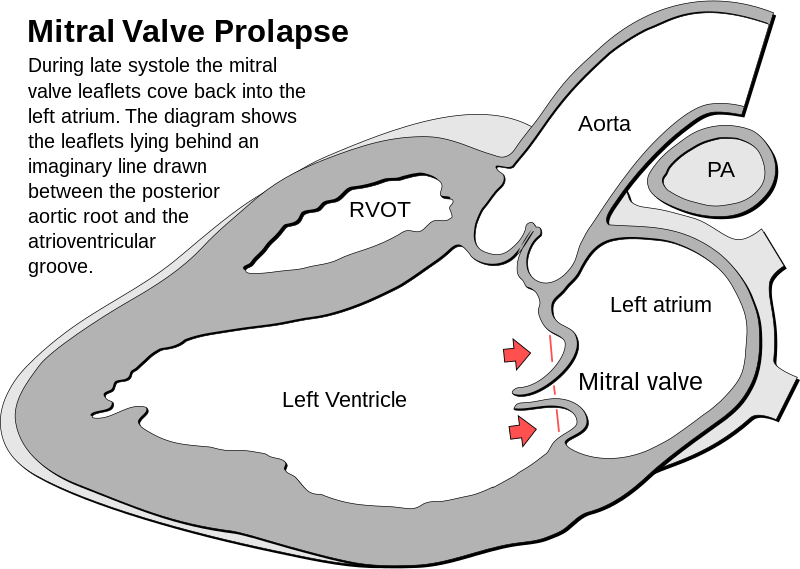

Mitral Valve Prolapse

Mitral valve prolapse is the ballooning of the mitral valve into the left atrium during systole.

Mitral valve prolapse is present in 2 – 3% of American adults due to myxoid degeneration of the mitral valve, which causes it to become floppy.

The cause of mitral valve prolapse is unknown, but is associated with myxoid degeneration.

Mitral valve prolapse is associated with two syndromes:

- Marfan syndrome

- Ehlers-Danlos syndrome

Mitral valve prolapse presents with an incidental mid-systolic click followed by a regurgitation murmur that is usually asymptomatic.

Squatting increases the click and murmur volume of mitral valve prolapse due to increased systemic resistance and slows left ventricular emptying.

Complications of mitral valve prolapse include:

- Infectious endocarditis

- Arrhythmia

- Severe mitral valve regurgitation

Treatment of aortic regurgitation is valve replacement.